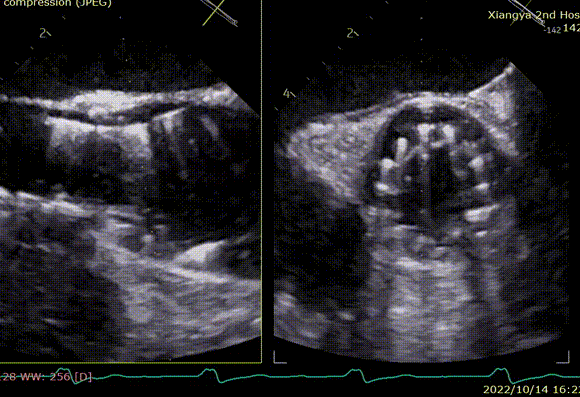

术后即刻评估

术后即刻TEE示主动面瓣膜最大峰值血流速为1.1m/s,平均跨瓣压差为2mmHg,少量瓣周漏。

术后即刻TEE示主动脉瓣膜最大峰值血流速为2.4m/s,平均跨瓣压差为11mmHg,支架内未见明显反流或瓣周漏。

术后即刻TEE示主动面瓣膜最大峰值血流速为2.1 m/s,平均跨瓣压差为8.6 mmHg,少量瓣周漏。